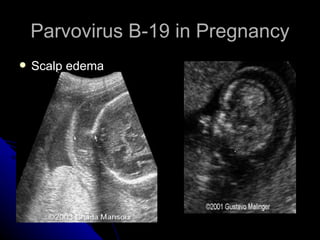

Parvovirus B-19 in Pregnancy Scalp edema

Parvovirus B-19 inPregnancy Scalp edema